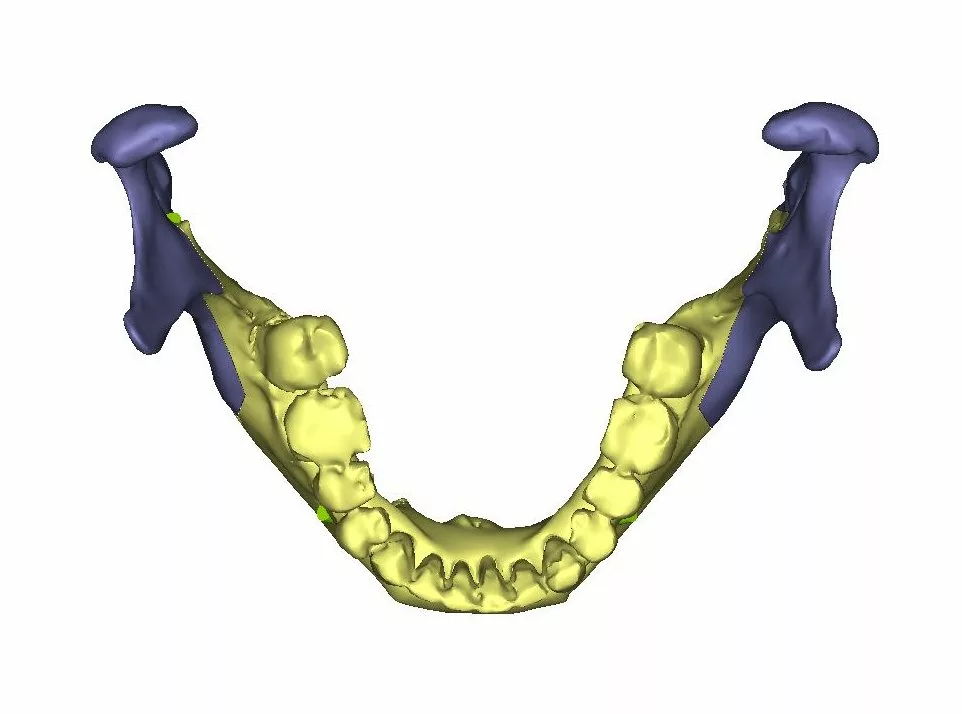

L’ostéotomie sagittale des branches montantes

Elle permet de déplacer l’ensemble de l’arc denté mandibulaire c’est à dire ensemble de « os basal – os alvéolaire – dents inférieures » dans les trois dimensions de l’espace.